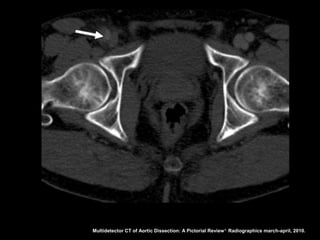

Definição da luz

•A luz falsa com frequência tem área transversal

maior devido ao fluxo lento;

• A luz verdadeira encontra-se comprimida em 80%

dos casos;

• A falsa luz tem maior propensão à trombose;

• Quando uma luz envolve a outra, a luz interna

invariavelmente é a verdadeira;

• O fluxo sanguíneo lento leva a retardo na

opacificação da luz falsa.

Multidetector CT of Aortic Dissection: A Pictorial Review 1. Radiographics march-april, 2010.